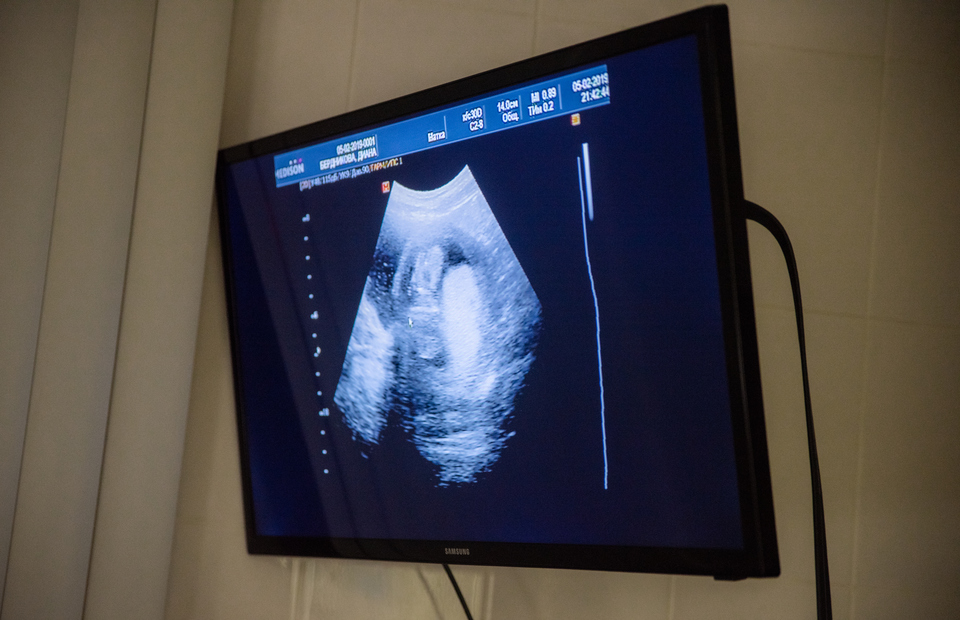

Совсем скоро Диана Бердникова в четвёртый раз станет мамой. Экс-участница шоу «Спаси свою любовь» уже воспитывает старшую дочь, а также двойняшек от брака с Сергеем. Сейчас у неё третья беременность, которая протекает не очень благополучно. Врач-гинеколог Оксана Валерьевна Богдашевская из Европейского лечено-диагностического центра «АТЕ клиник» советует Диане тщательно наблюдаться у высококлассных докторов, поскольку у неё есть угроза выкидыша.

«Диана встала на учёт по беременности и сдала комплекс первичных анализов. Она не очень социальная девочка. Только благодаря мужеству и высокому профессионализму врачей Приморского края её двойняшки живы. У неё отрицательный резус-фактор крови, с ней надо работать и работать надо!» — объяснила Оксана Валерьевна Dom2Life.ru.

Оказывается, Бердникова родила двойняшек не самостоятельно, а с помощью кесарева сечения. Её последующая беременность наступила гораздо раньше срока, который считался бы нормой для очередного зачатия после такой операции.

«У Дианы молодой рубец на матке, потому что прошло чуть больше года после кесарева сечения по экстренным показаниям, спасали жизнь малышам, — продолжает Богдашевская. — Рубец не успел восстановиться. А должно пройти 24 + 9 месяцев от кесарева сечения до новых родов. Минимум год ещё надо было предохраняться…

Вторая проблема Дианы — отрицательный резус крови. Надо сдавать кровь на резус-антитела чётко в обозначенные приказом сроки, чтобы не пропустить развитие резус-конфликта. Диана нуждается в очень тщательном и экспертном наблюдении, ей нужно наблюдаться на уровне перинатального центра. Потому что это беременность высокого риска».

Врач подчеркнула, что Бердникова может родить здорового малыша только при условии, если будет выполнять все рекомендации специалистов. В свою очередь центр «ATE клиник» располагает всем необходимым оборудованием, чтобы обеспечить Диане благополучное вынашивание малыша.